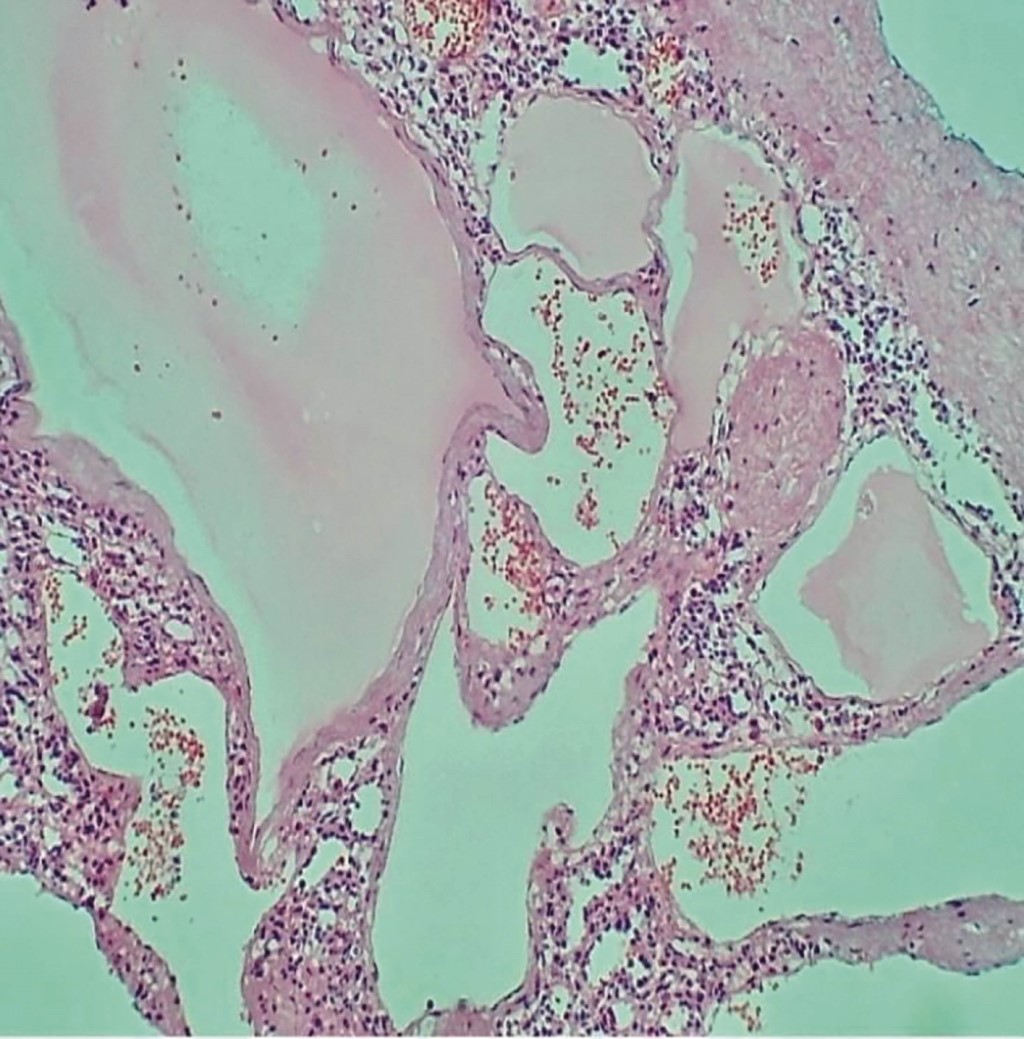

Presentamos el caso de una mujer de 27 años de edad sin antecedentes cronicodegenerativos ni quirúrgicos de importancia. Inició su padecimiento de un mes de evolución, con presencia de cefalea leve, malestar al comer y náuseas, por lo que acudió a valoración médica no especializada. Se prescribe una ecografía abdominal que reporta un tumor esplénico como hallazgo principal. Es referida a consulta médica de especialidad en cirugía general. A la exploración física se encontró abdomen globoso a expensas de visceromegalia, blando, pero no depresible en cuadrante superior y flanco izquierdos, no doloroso, sin datos de irritación peritoneal, extremidades íntegras, con hipotonía en extremidad pélvica izquierda y presencia de hemangioma subcutáneo en miembros pélvicos, sin limitación en los arcos de movimiento. Se realizaron estudios de laboratorio que reportaron de relevante sólo anemia leve (11.6 g/dL) y leucopenia (3.2 × 109/L). La tomografía de abdomen simple reportó esplenomegalia severa, con múltiples imágenes nodulares e hiperdensas, asociado a heterogeneidad del plano graso peritoneal del interior del hueco pélvico, observando imágenes nodulares hiperdensas sugerentes de tejido ganglionar calcificado (Figura 1). Se decidió programar a la paciente para esplenectomía laparoscópica mano asistida por el tamaño del tumor, previo protocolo quirúrgico completo se ingresó a paciente a quirófano, se inició procedimiento, con abordaje laparoscópico abierto, supraumbilical y en línea media con incisión de 8 cm disecando por planos hasta la cavidad, bajo visión directa se colocaron trocares de trabajo, disección mano asistida de hilio esplénico y las fijaciones ligamentosas con energía ultrasónica y bipolar avanzada presentando hemostasia difícil debido a las dimensiones del bazo. Se colocaron Hem-O-Locks proximales y distales, así como clips de titanio, obteniendo hemostasia, se introdujo pieza quirúrgica en bolsa extractora, y se extrajo de la cavidad peritoneal mediante morcelación manual, sin complicaciones, se verifica hemostasia y limpieza de cavidad con 3 litros de solución estéril (Figura 2). Se retiraron trócares y se afrontaron incisiones por planos. La paciente se mantuvo con evolución favorable durante su estancia hospitalaria, sin referir ninguna sintomatología, se egresó al tercer día del periodo posquirúrgico. El resultado de patología reportó bazo multifragmentado y deformado, 33 × 20 × 8 cm de tamaño, peso de 1,180 gramos, con linfagioma esplénico difuso, áreas de parénquima esplénica con esplenitis crónica con congestión y dilatación vascular (Figuras 3, 4 y 5). Se continuó con seguimiento por la consulta externa a los siete y 21 días de la cirugía con evolución favorable. Al día 10 se sometió a doble esquema de vacunación contra Streptococcus pneumonie (Neumococo) y Neisseria meningitidis (Meningococo) sin eventos adversos.

Figura 1

Figura 2

Figura 3

Figura 4

Figura 5